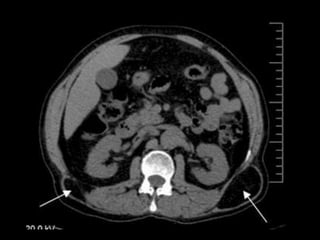

Hernias lumbares

• -2%

Congénitas 10%

Grynfelt : Tríangulo superior de la región lumbar

Cuadro clínico

• Asintomáticas

• Aumento progresivo de volumen pequeño o

grande en la región de alguno de los flancos

• Riesgo de encarceración es de 25%

• Estrangulación 8-18%

• Más frecuente en las congénitas y en las

incisionales con múltiples operaciones y

anillos fibróticos poco distendibles

Métodos diagnósticos

• En pacientes muy obesos y con sacos herniarios

muy pequeños.

• USG dinámico, en reposo y con maniobra de

valsalva

• TAC dinámica